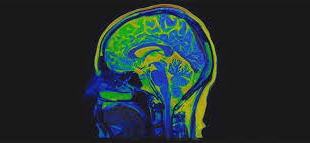

Warning of serious brain disorders in people with mild coronavirus symptoms

UK neurologists publish details of mildly affected or recovering Covid-19 patients with serious or potentially fatal brain conditions Doctors may be missing signs of serious and potentially fatal brain disorders triggered by coronavirus, as they emerge in mildly affected or recovering patients, scientists have warned. Neurologists are on Wednesday publishing ... Read More »